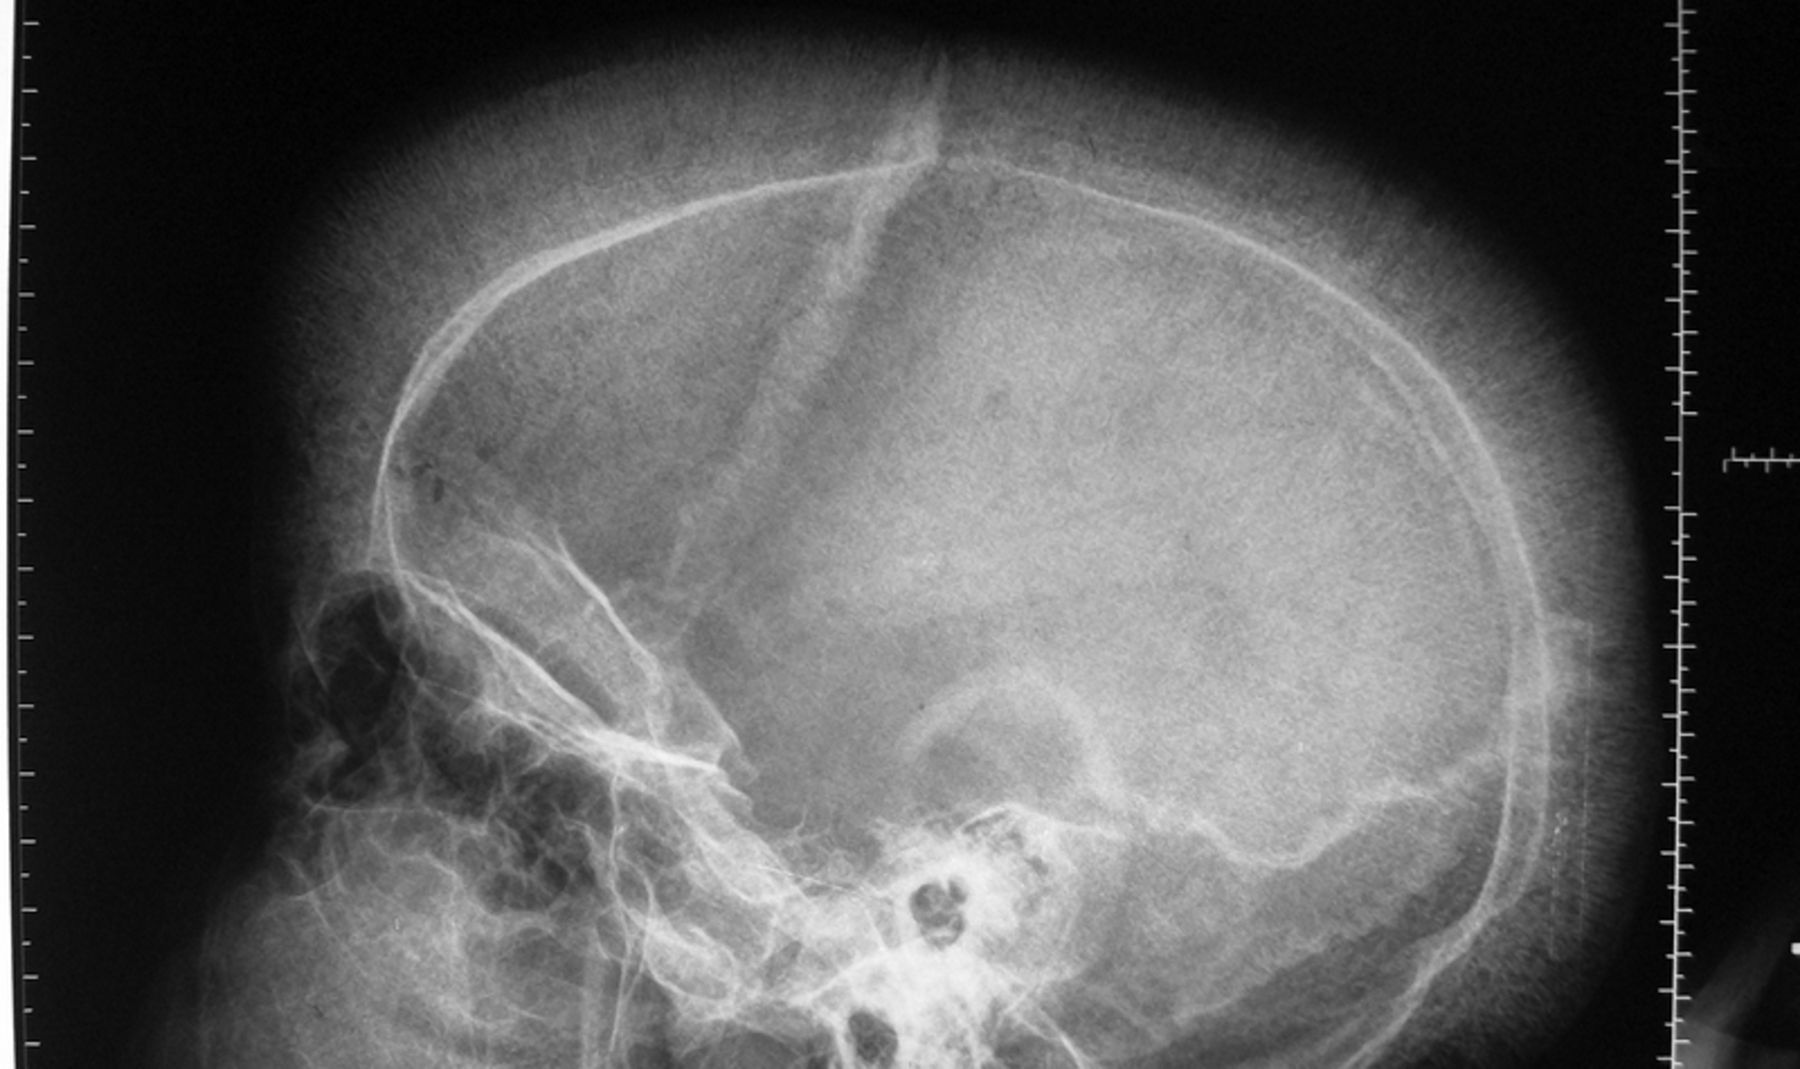

Beta Thalassemia is an autosomal recessive disorder. The crew cut appearance of skull on X ray and hepatosplenomegaly are seen in this disorder due to extra-medullary hematopoiesis. Some other diagnostic features of Beta Thalassemia Major are evidence of severe red cell dysplasia, erythroblastosis, evidence that both parents have thalassemia minor,profound hypochromic anemia, absence or gross reduction of the amount of hemoglobin A and raised levels of hemoglobin F on Hb electrophoresis